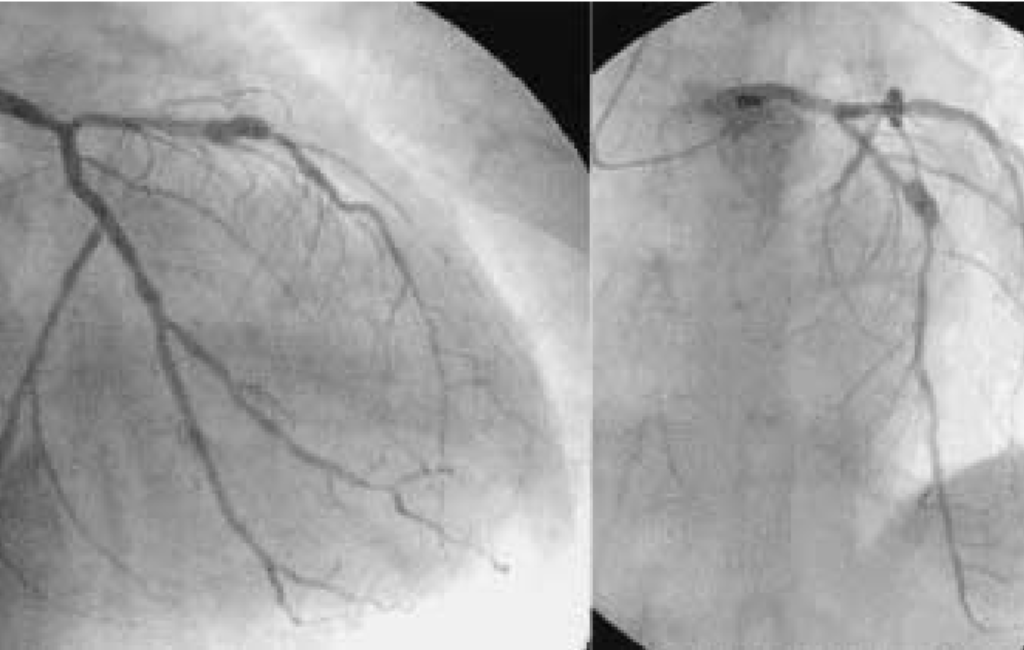

Coronary Artery Bypass Grafting (CABG) – Heart Bypass Surgery

• Minimally Invasive CABG – Lower risk, faster healing, and less post-op pain.

• Traditional Open-Heart Bypass Surgery – Restoring blood flow to blocked arteries.

Angioplasty & Stent Placement – Restoring Blood Flow to the Heart

• Balloon Angioplasty & Stenting – Non-surgical, quick recovery treatment for heart blockages.